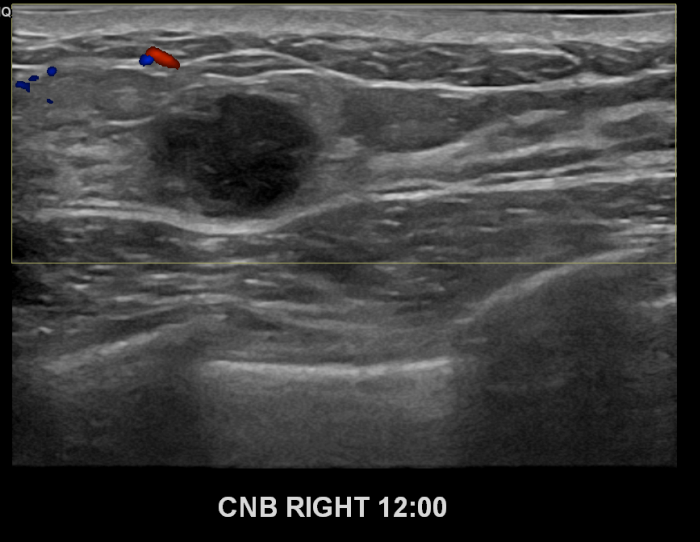

상기환자 만져진멍울있어 내원하신 40대여성분으로 우측유방

의심스러운 혹 조직검사시행후 유방암 진단되었습니다